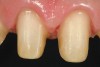

Figure 1  Preoperatively, the patient‚Äôs smile showed a full gingival display and asymmetrical gingival levels in the maxillary anterior region. Although the ‚Äúgummy smile‚Äù may not be able to be eliminated completely, better symmetry of the tissue levels was one of the goals of treatment.

Figure 1